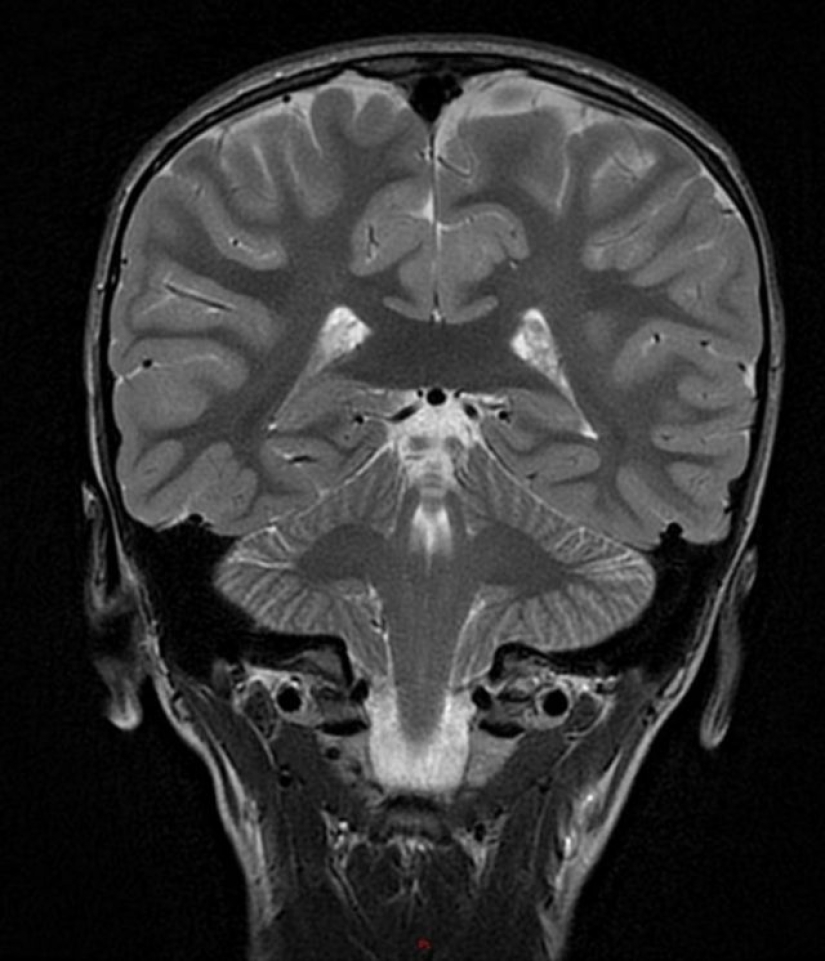

2. “Apparently, there is a little boy in my son’s brain. And it's not photoshop.